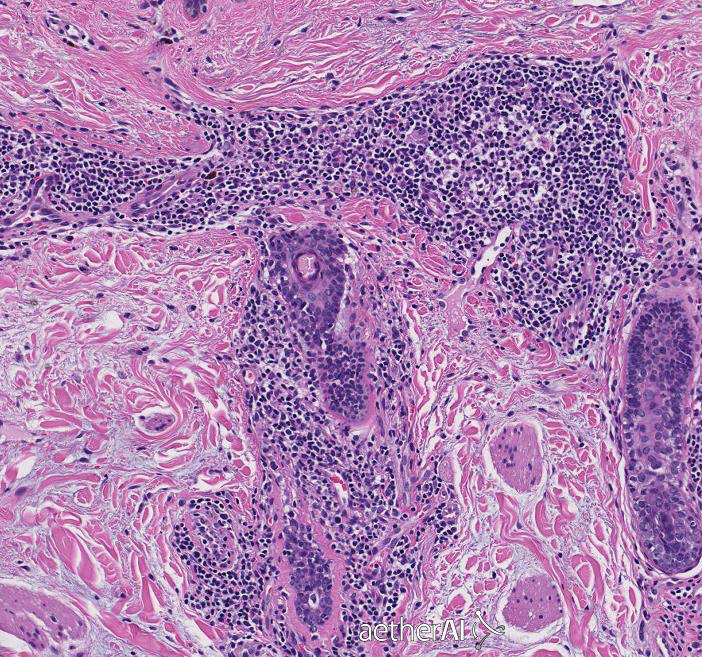

ALOPECIA AREATA